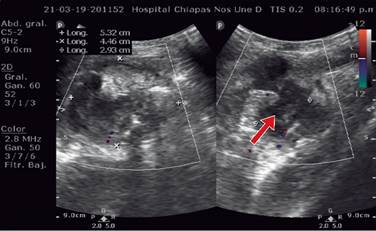

Masculino de nueve años con antecedente de haber sido intervenido quirúrgicamente por apendicitis aguda dos años y medio previos a su padecimiento actual, el cual inicia 10 días antes de su ingreso y se caracteriza por dolor abdominal generalizado y vómitos en dos ocasiones de características gastroalimentarias, manejado por facultativo con analgésicos no especificados y sin mejoría. Continúa con dolor abdominal de predominio en el cuadrante inferior derecho acompañado de náuseas y vómitos. Motivo por el cual acude al Servicio de Urgencias del hospital, en donde se encuentra al paciente con dolor en cuadrante inferior derecho, posición en gatillo y con datos de irritación peritoneal. Se solicitan laboratoriales, reportándose hemoglobina de 13.0 mg/dl, hematocrito de 38.2%, 15.15 × 109, 76.4% neutrófilos. La placa simple de abdomen muestra una imagen de asa fija en fosa iliaca derecha (Figura 1). Se solicita ultrasonido abdominal, el cual reporta una colección de 5 × 4 cm (Figura 2), por lo que se interconsulta al Servicio de Cirugía General ya que no se contaba con cirujano pediatra en el turno; 24 horas después de su ingreso es valorado por cirugía, encontrando al paciente con discreta resistencia voluntaria en cuadrante inferior derecho e irritación peritoneal. Se solicita una resonancia magnética abdominal, para determinar la probable etiología de la colección, la cual reporta una colección amorfa en fosa iliaca derecha, de bordes irregulares y bien definidos, con medidas de 5.1 × 4.3 × 4.9 cm en sus diámetros longitudinal y anteroposterior transverso, respectivamente, compatibles con absceso en fosa iliaca derecha.

Figura 2: Estudio ultrasonográfico que muestra una colección líquida a nivel de cuadrante inferior derecho. La flecha señala la colección.